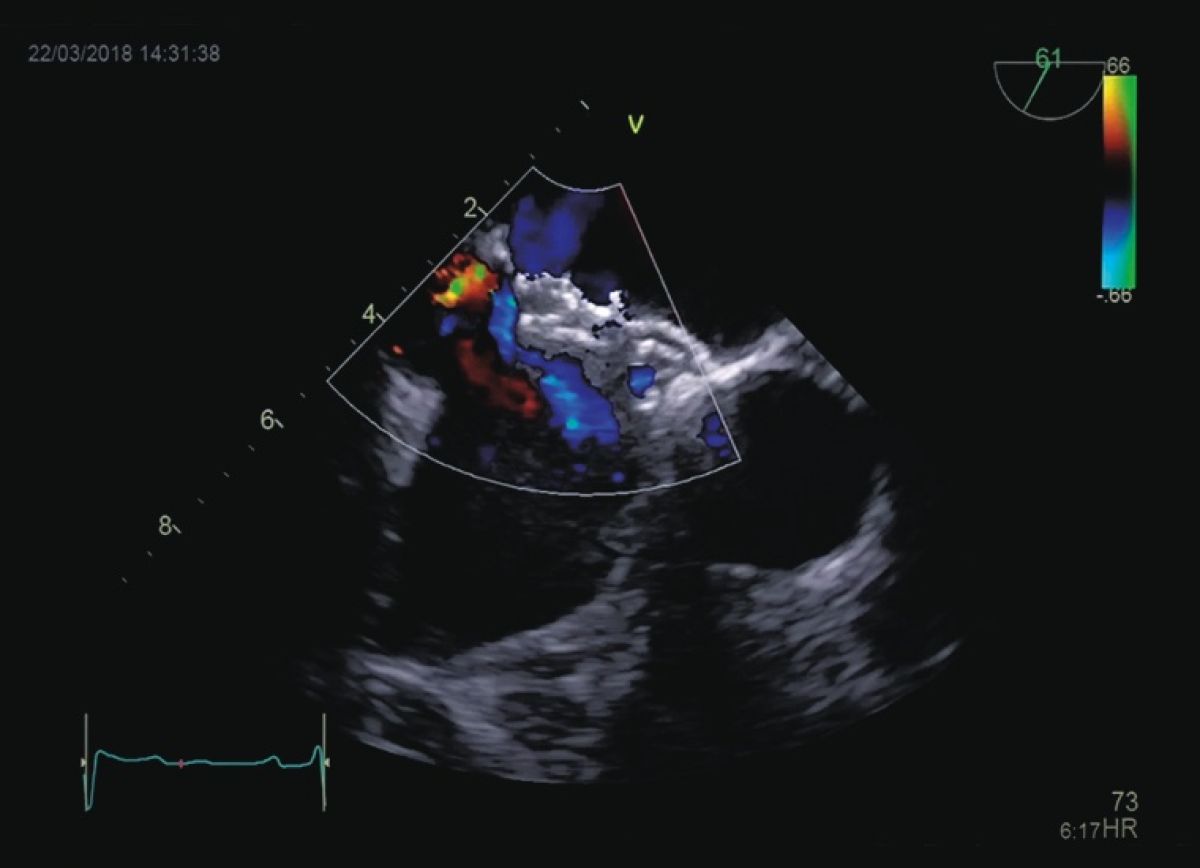

Pacjentka z pogorszeniem tolerancji wysiłku, kołataniami serca i cichym szmerem skurczowym

Ubytek w przegrodzie międzyprzedsionkowej typu otworu wtórnego

Ocena ubytku w przegrodzie międzyprzedsionkowej

Ocena prawych jam serca

Kwalifikacja do przezskórnego zamknięcia ubytku w przegrodzie międzyprzedsionkowej